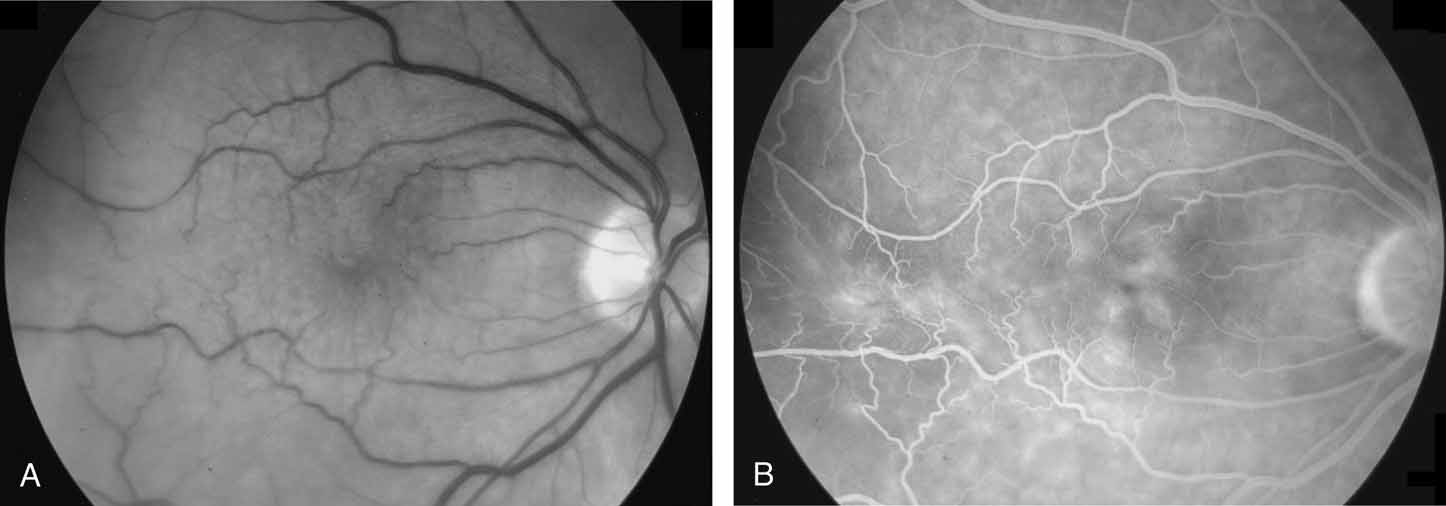

Chronic macular holes are generally considered to be stage 3 or stage 4 holes that have been present for more than 1 year. These holes, possibly due to long-term intraretinal fluid accumulation, epiretinal membrane formation, and RPE atrophy are more difficult to close compared to acute macular holes. Fortunately, because of increased awareness of macular holes by the general ophthalmic community, chronic holes are becoming far more rare. Visual improvement may occur with successful hole closure. However, these improvements are generally not as pronounced as those seen with acute macular holes. Roth et al.62 were able to close 9 of 11 chronic holes in their series, with a mean postoperative vision of 20/100. ILM peeling, adjuvants, and endolaser may assist in macular hole closure in this challenging subgroup.